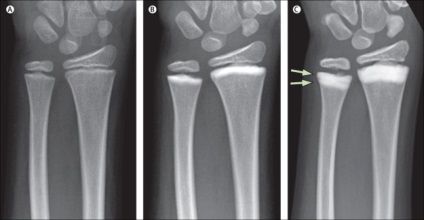

Az állam a csontok röntgen

A betegség súlyosságától abban a tényben rejlik, hogy a születési időt, nem nyilvánul meg. A beteg egy kicsit, hogy jól érzik magukat. Általános szabályként, az azonosítás a betegség előfordul, véletlenszerűen, a beteg jön a klinikára vizsgálatot, arra irányul, hogy egy X-ray, és ekkor, diagnosztizáltak osteosclerosis.